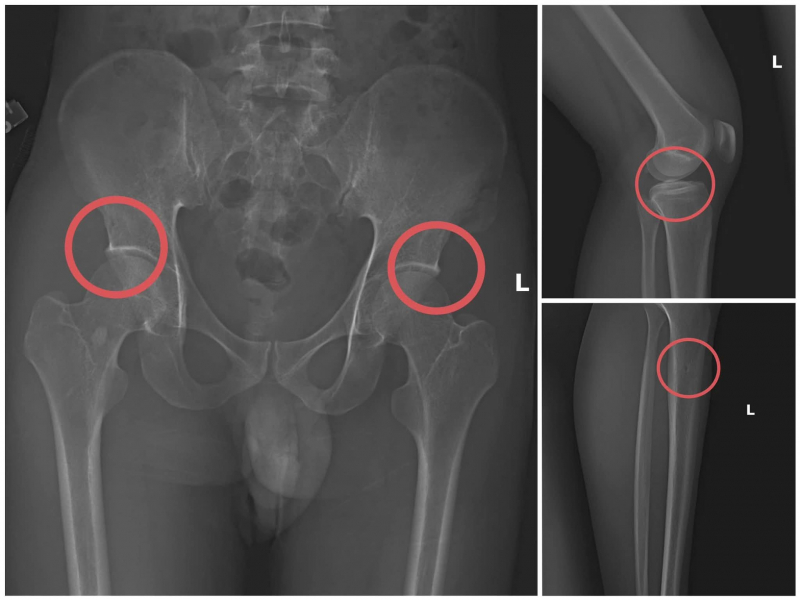

Nhóm đối tượng thực hiện hành vi tiêm thuốc mê, rồi dùng kim tiêm, búa, đinh để tác động vào xương người mua bảo hiểm, tạo nên các vết nứt, vỡ xương tương tự tai nạn thật.

Đối tượng Châu trực tiếp thực hiện hành vi tiêm thuốc mê, rồi dùng kim tiêm, búa đinh để tác động vào xương người mua bảo hiểm, tạo nên các vết nứt, vỡ xương tương tự như tai nạn thật. Khi thương tích đã tạo xong, đối tượng Châu tiếp tục hướng dẫn các đối tượng dựng hiện trường giả như điện giật ngã, trượt chân ngã suối nhằm hợp thức hóa bệnh án và hoàn thiện hồ sơ yêu cầu chi trả.

Theo Công an tỉnh Phú Thọ, thủ đoạn này vừa tàn nhẫn, vô nhân tính, coi thường sức khỏe, tính mạng của người tham gia, vừa được tính toán kỹ để gây thương tích đúng vị trí có mức chi trả cao, khiến các công ty bảo hiểm khó phát hiện dấu hiệu gian dối.